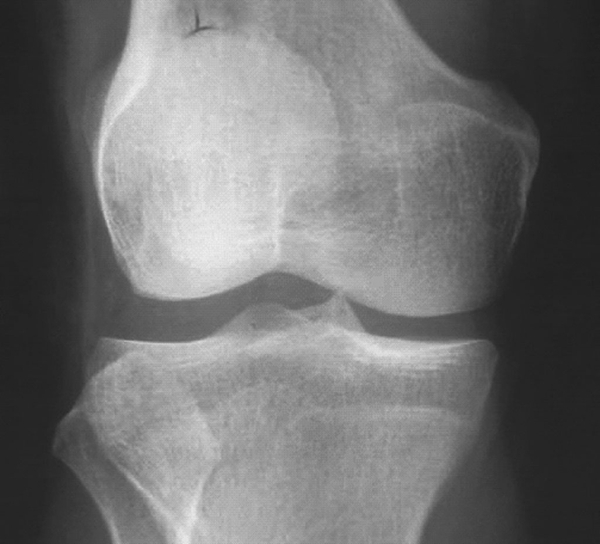

X平片常表现不明显,可有患肢外侧关节间隙增宽,胫骨髁间棘高尖及腓骨小头高位等征象(图4-10-1-2)。但X线诊断盘状半月板特异性不够,仍需辅助检查。

图4-10-1-2 右膝外侧盘状半月板,外侧间隙明显增宽